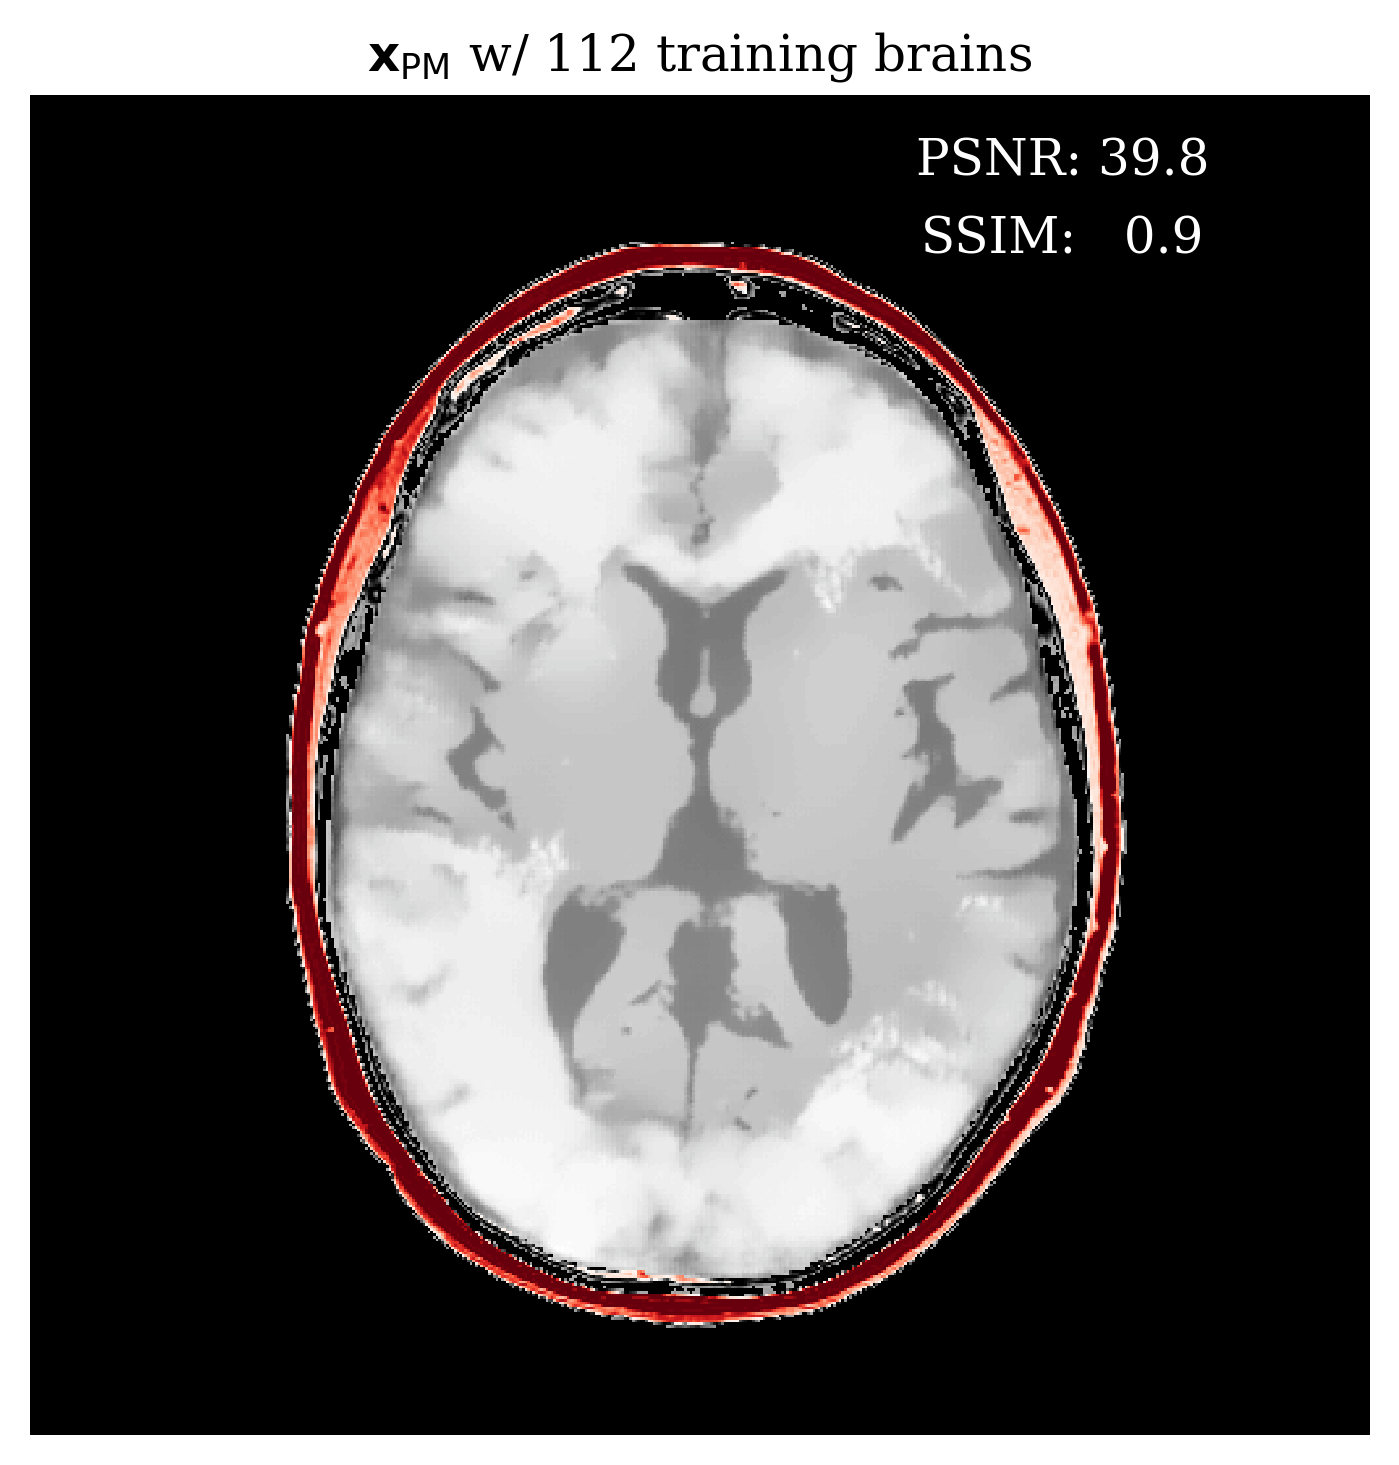

3.2 Image reconstruction from posterior samples

Once trained, our conditional normalizing flow can generate samples from the posterior with Algorithm 2. The computational cost of posterior sampling is dominated by the calculation of the physics-informed summary . This takes second per source and seconds in total for all sources (on 4 core Intel Skylake CPU). This calculation only needs to be done once per ultrasound experiment after which many posterior samples can be generated each at the cheap cost of one inverse network evaluation (20ms/sample). With these posterior samples, statistical point estimates can be calculated including the minimum mean squared error (MMSE) estimator given by the posterior/conditional mean that serves as our image reconstruction. For UQ, we look at the intra-sample variation between posterior samples. To visualize UQ on the entire image reconstruction we use the posterior variance . The posterior mean (and variance) is calculated by approximating their expectations with an average over posterior samples

See Appendix 4.7 for an analysis of the quality of as the number of posterior samples increases. In this work, we concentrate on the posterior mean because it is the estimator with minimal mean squared error Whang et al. (2021). Figure LABEL:fig:basic contains an example of the input and output of the proposed image reconstruction algorithm including UQ.

To assess the performance of our reconstruction, , we compare with two baseline methods, namely physics-only FWI, yielding obtained by gradient descent, and a supervised U-Net Ronneberger et al. (2015) trained on the same data pairs as our method. Compared to the learned methods, which incur off-line training costs prior to inference, FWI is computationally intensive since it requires calls to the forward and gradient for each source while our method only requires one gradient per source. Refer to Appendix 4.3 for FWI and network training hyperparameters.

fig:compare

From Figure LABEL:fig:compare, we make the following observations: (i) our result contains fewer artifacts compared to FWI; (ii) it performs better than U-Net; (iii) it captures the full posterior yielding pointwise variances that correlate well with error; (iv) due to averaging over posterior samples our result blurs a few details as compared to FWI. For a more quantitative comparison of the reconstruction quality, refer to \tablereftab:timing in which the average quality metrics for peak signal to noise ratio (PSNR); structural similarity index metric (SSIM); and root mean squared error (RMSE) are computed from unseen test slices. Our method shows high performance on all metrics while keeping the online inference time significantly lower than the FWI method. For more direct comparison, we avoided measurement noise.